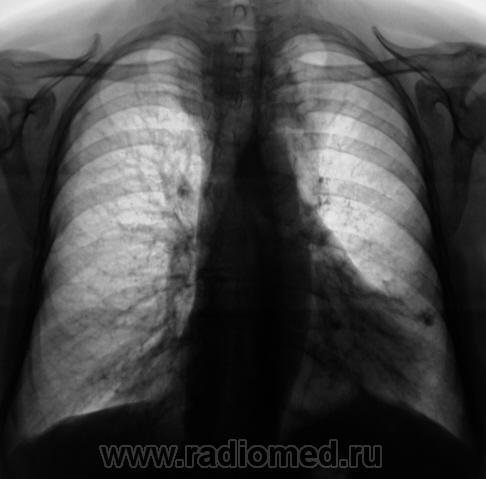

Пациента в течение месяца "лечили" противотуберкулёзными препаратами. Произведен контроль "в динамике".

Валентин Львович, а какие снимки до, а какие после лечения? Я какой-либо динамики не вижу

Первые - до, нижние после.

На мой взгляд, слева на верхушке в медиальных отделах верхушеного сегмента (1+2) некоторая динамика есть, да и "кругляк" справа на верхушке (средостении) на 11 срезе, субъективно дифференцируется лучше.

Синяя стрелка, как понимаю "кругляк", который смущает Валентина Львовича? К сожалению край изображения, тяжело что-то понять. Вероятнее всего это 1 ребро.

Зато Красная стрелка - явно зоб